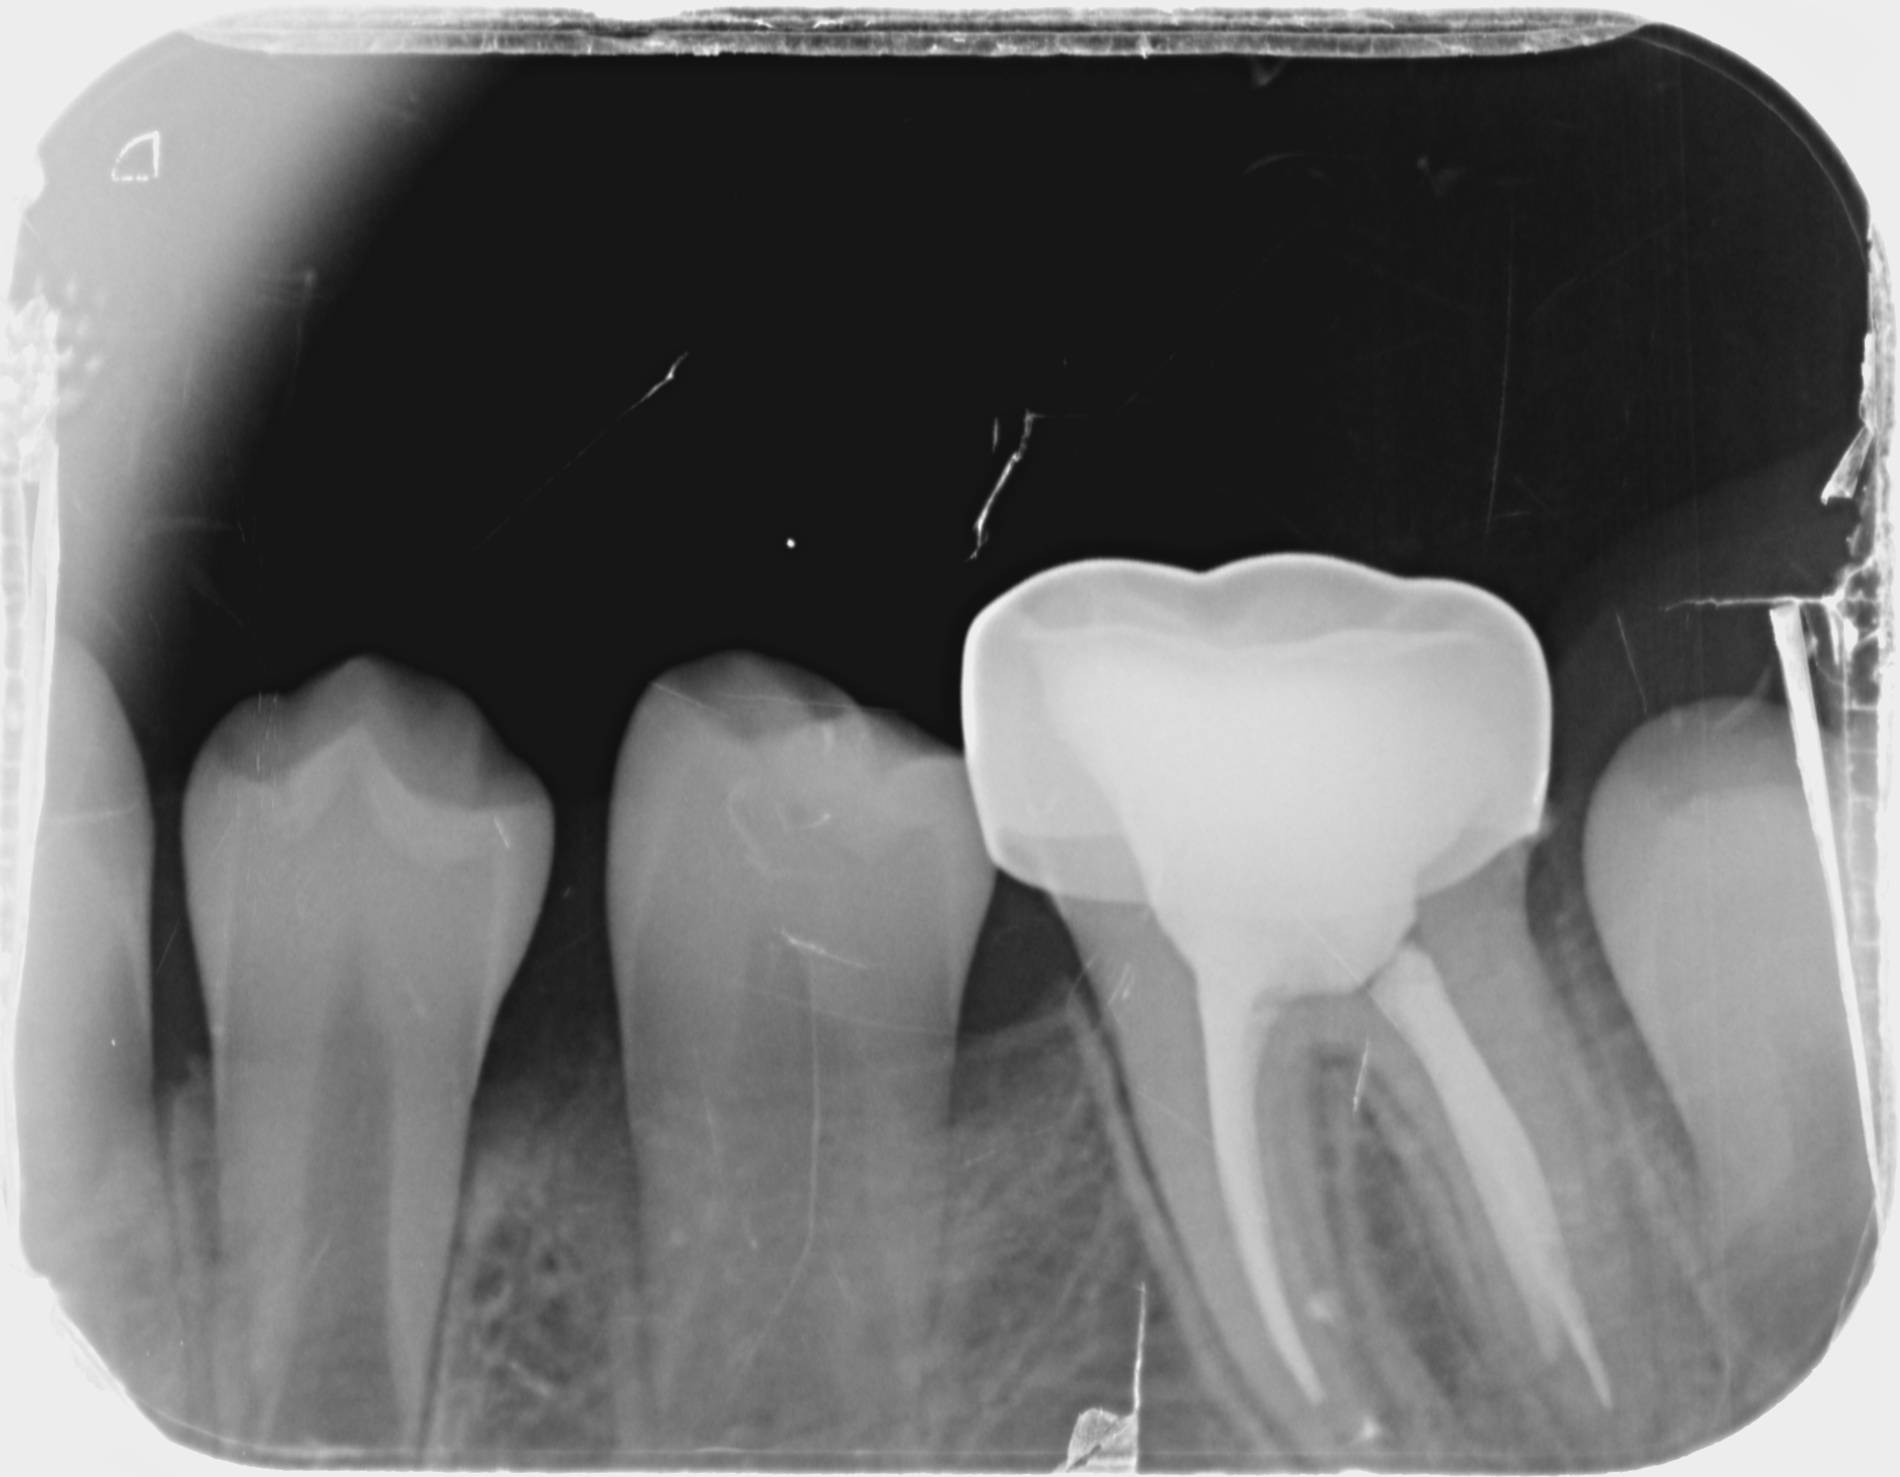

환아의 치료 전, 엑스레이와 구강 내 사진입니다. 거의 모든 치아에 충치가 있습니다. 특히 아래 어금니는 치아의 절반 넘게 충치로 깨져 없어진 상태입니다. 무서워서 빼야 할 시기를 한참 넘긴 남아있는 유치들도 많습니다. 그리고 영구치 윗니 앞니에 사이 충치가 보이네요.

치료 후. 깨끗하게 신경치료 후 잘 기능할 수 있도록 영구치 SS 크라운을 씌워줬습니다. 아이가 다 성장하고 교합이 완성되면 성인 보철이 한번 필요합니다.

이후, 정기 검진을 와서 찍은 치료 후 사진과 비교입니다.

충치가 심해 신경치료 한 치아에도 염증이 없고 잇몸도 잘 나아서 깨끗해진 치아를 보니 다행이다 싶고 보람있습니다.^^